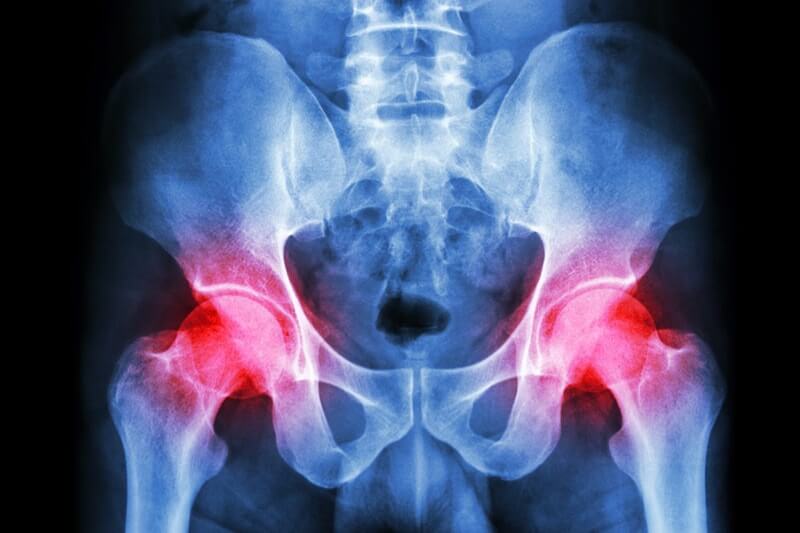

DOLOR PÉLVICO

¿Es normal? En general, no. “Hay muchas causas potenciales de dolor pélvico, que varían desde causas ginecológicas, como enfermedades por transmisión sexual, enfermedad inflamatoria pélvica o endometriosis, hasta afecciones intestinales como el SII, explica el consultor ginecólogo y obstetra Eleni Mavrides.

¿Cuándo es serio? La regla de oro es que debes acudir al médico si sientes el dolor pélvico; independientemente de si es grave o persistente. “La enfermedad inflamatoria pélvica (EIP) es difícil de reconocer, pero puede tener consecuencias devastadoras para la fertilidad si no se atiende”, dice Mavrides. “Algunas mujeres experimentan dolor o molestias alrededor del abdomen o durante las relaciones sexuales como resultado de la EIP. Pero, otras no experimentan ningún síntoma en absoluto”.